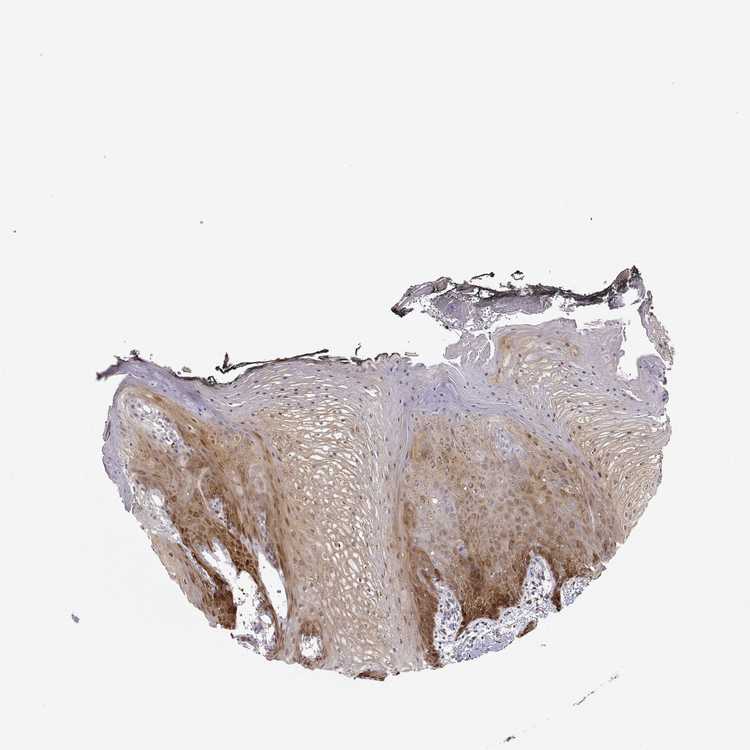

TISSUE PRIMARY DATA ORAL MUCOSA Show tissue menu

Oral mucosa

ORAL MUCOSA - Antibody stainingi

Antibody staining in the annotated cell types in the current human tissue is reported as not detected, low, medium, or high, based on conventional immunohistochemistry profiling in selected tissues. This score is based on the combination of the staining intensity and fraction of stained cells.

Each image is clickable and will lead to virtual microscopy that enables deeper exploration of all samples and also displays staining intensity scores, fraction scores and subcellular localization as well as patient and tissue information for each sample.

Antibody HPA007308Antibody CAB012421

Squamous epithelial cells HighMedium